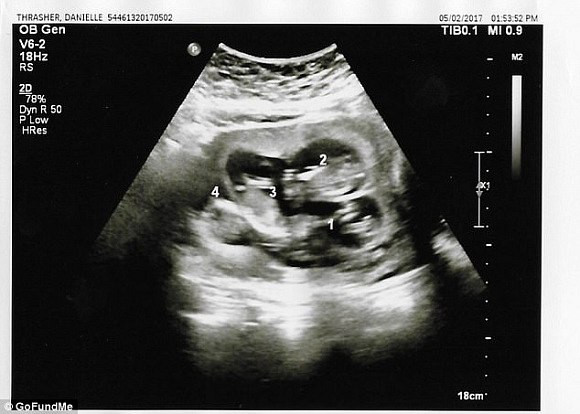

Thế nhưng, tuần thai thứ 13, trong một lần siêu âm, chị nhận được kết luận của bác sĩ rằng trong bụng chị đang có tới 4 bào thai đang phát triển. Thay vì ngỡ ngàng như lần trước, Joseph đã rất điềm tĩnh để chấp nhận chuyện này. Chồng chị Danielle nói: “Mặc dù chấp nhận điều này đồng nghĩa với việc hai đứa đã chuẩn bị tinh thần cho một cuộc sống có nhiều khó khăn về kinh tế phía trước nhưng chúng tôi sẽ cố gắng vì gia đình nhỏ của mình”.

Lần siêu âm thứ 3 thì các bác sĩ mới phát hiện ra em bé thứ tư.

Bác sĩ khám cho Danielle giải thích lý do tại sao đến lần siêu âm thứ ba mới phát hiện mang thai 4: “Bào thai thứ tư bị che khuất bởi lỗ rốn của Danielle, điều đó khiến chúng tôi không thể nhìn thấy trong những lần siêu âm trước. Còn việc mọi người hỏi rằng tại sao không kiểm tra kĩ trong quá trình siêu âm thì chúng tôi cho rằng việc thai phụ có 3, 4 hay 5 con không nằm trong dự đoán của chúng tôi và chúng tôi không có bất cứ lý do nào để kiểm tra xem liệu thai phụ đang mang bao nhiêu thai, nhất lại là trong những trường hợp như thế này, vị trí nằm của đứa trẻ không khiến chúng tôi đặt bất cứ nghi vấn nào”.